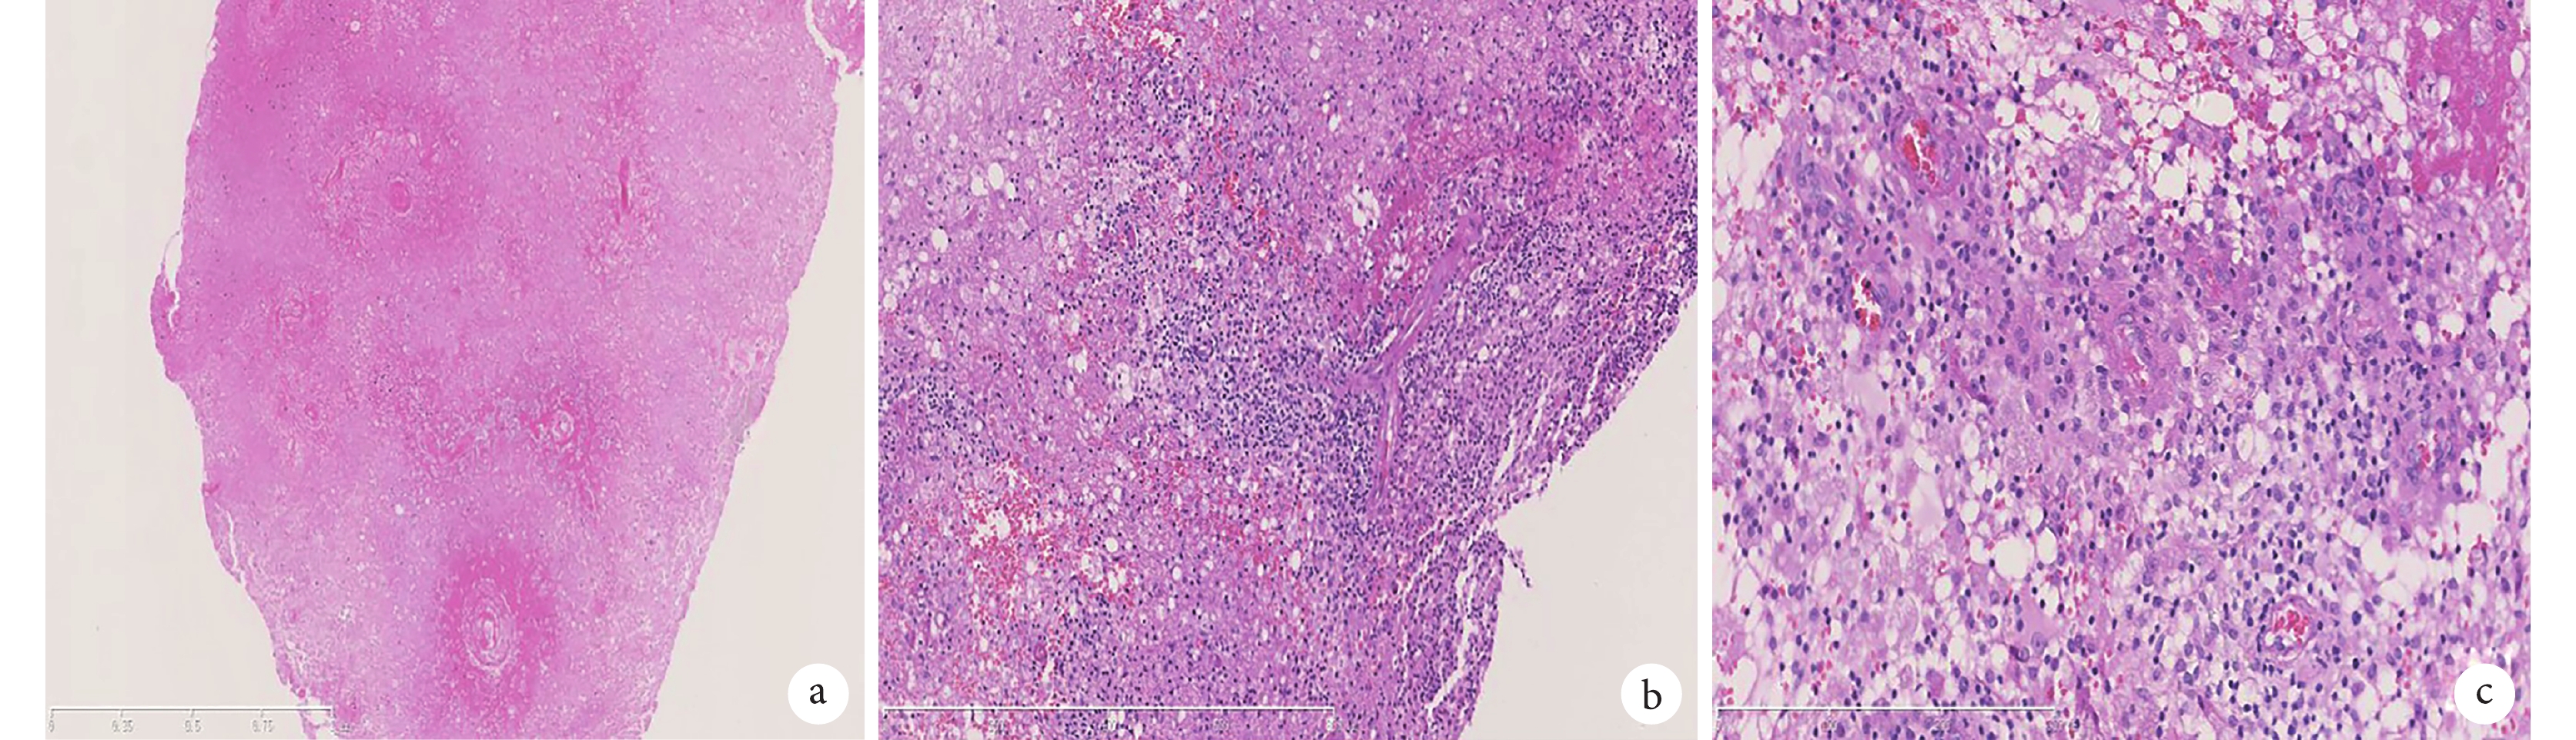

HE 染色示所檢組織內大片壞死;小血管周圍可見大量淋巴細胞浸潤;部分血管壁纖維素樣壞死;a. HE ×50;b. HE ×100;c. HE×200

入院后診療經過:入院后完善輔助檢查。實驗室檢查:血漿乳酸 4.59 mmol/L,余實驗室檢查無異常。視覺誘發電位、腦干誘發電位未見異常,心臟、腹部、泌尿系統彩色多普勒超聲(彩超)未見異常。頸部淋巴結彩超:淋巴結稍增大。婦科彩超:宮內環、子宮多發肌瘤。胸部 CT:右肺中葉外側段、右肺下葉胸膜下小結節,多系炎性結節。頭部 MRI:腦白質多發異常信號,部分強化,考慮多發性硬化。左側半卵圓中心強化結節,瘤樣脫髓鞘改變?腫瘤性病變?(圖 1i、1j)。完善上述檢查患者顱內強化結節診斷不明確,請神經外科會診完善病理活檢,會診后考慮顱內病變膠質瘤不排除,與患者家屬溝通后決定予以手術切除病灶。術后病理:腦組織廣泛壞死,部分小血管管腔閉塞,中等大小的小血管壁內見一些淋巴細胞浸潤,部分可疑纖維素樣壞死(圖 2),考慮為原發性中樞系統血管炎(primary angiitis of the central nervous system,PACNS)。術后予以潑尼松片 60 mg、1 次/d,復方環磷酰胺片 50 mg、2 次/d,口服治療,患者右下肢無力及行走不穩逐漸好轉,于 2017 年 1 月出院。出院后 1 年隨訪患者,患者未再訴行走不穩及右下肢乏力,生活自理,無服藥副作用,預后良好,但患者有癇性發作 1 次,目前加用丙戊酸鈉緩釋片對癥治療,繼續隨訪患者病情變化。